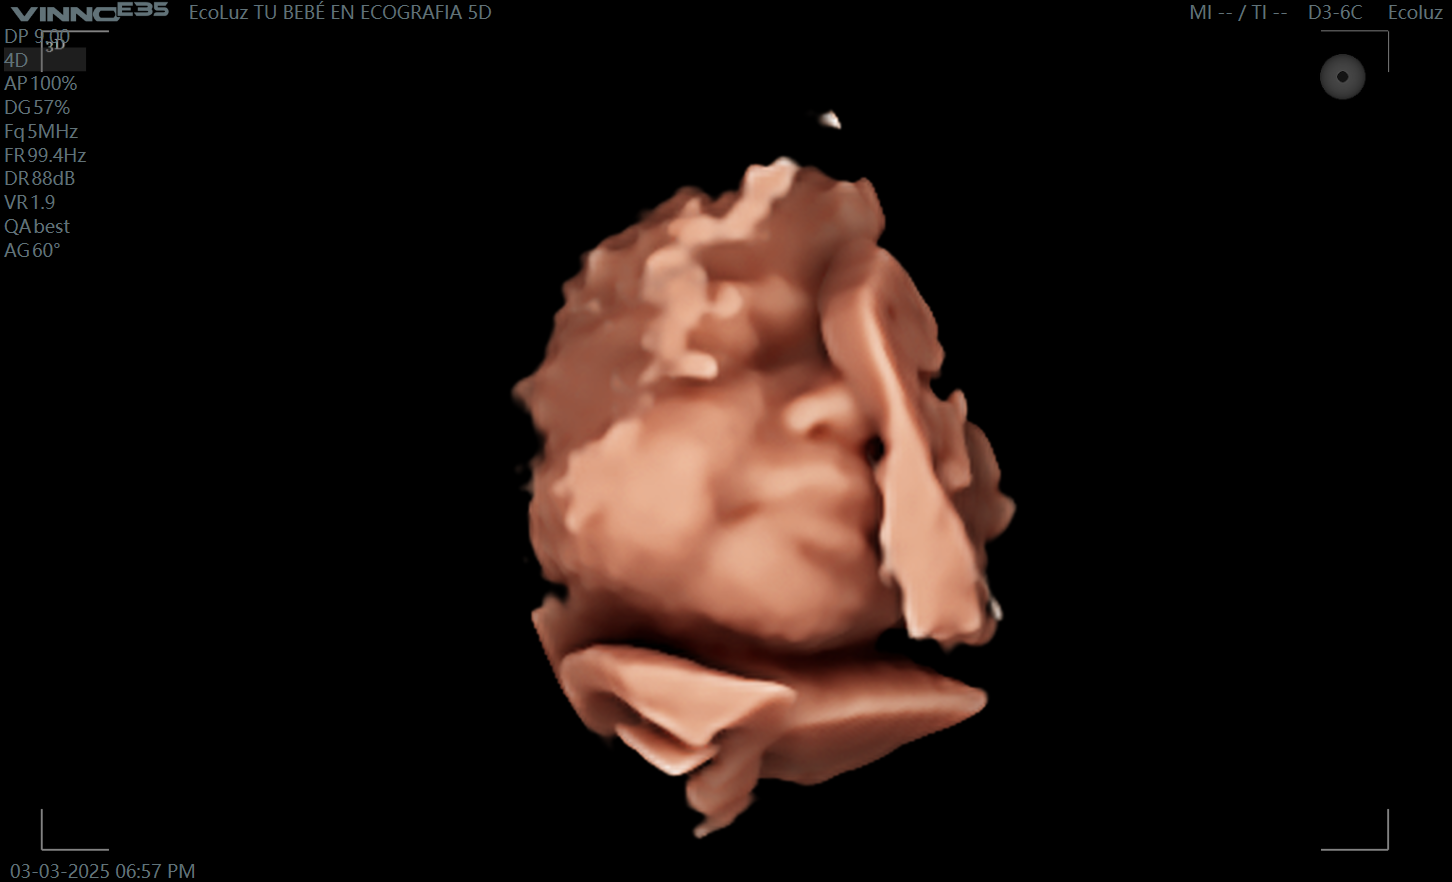

La ecografía de 30 semanas destaca porque el bebé ya tiene un aspecto más relleno y adorable. Es una etapa perfecta para crear un recuerdo visual inolvidable junto a tu…

A las 30 semanas, tu bebé ya tiene una apariencia muy similar a la que tendrá al nacer. La eco 30 semanas permite disfrutar de imágenes claras, emotivas y llenas…

La ecografía embarazo 30 semanas es perfecta para vivir una experiencia especial en el tercer trimestre. Ver su carita casi lista para el nacimiento es un momento inolvidable. 💓 En…